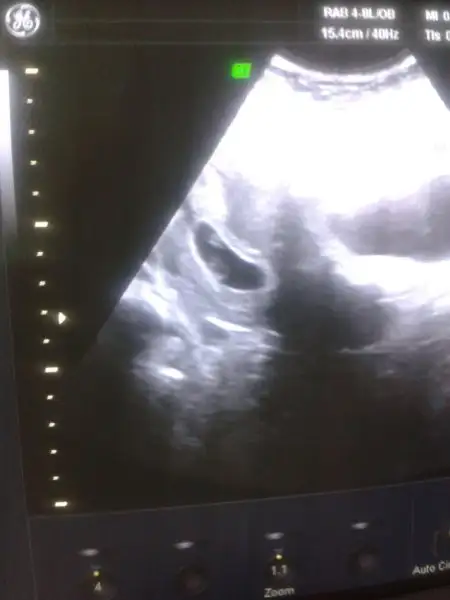

bana yorum yok mu 9 haftalik karından usg

Havalianne__ Can'ım birsey danışmak istiyorum benim ilk usg 5+5 günlükken ondan Bebek solda ( yani vajinal bakılmıştı ve sağdaydı ) erkek olabilir dediniz şimdi Bebek 8+3 olmuş bugun ve karıbdab usg ile sağda yani buna göre kız ihtimali yüksek sence hangi haftayı dikkate almalıyım çok teşekkürler şimdiden